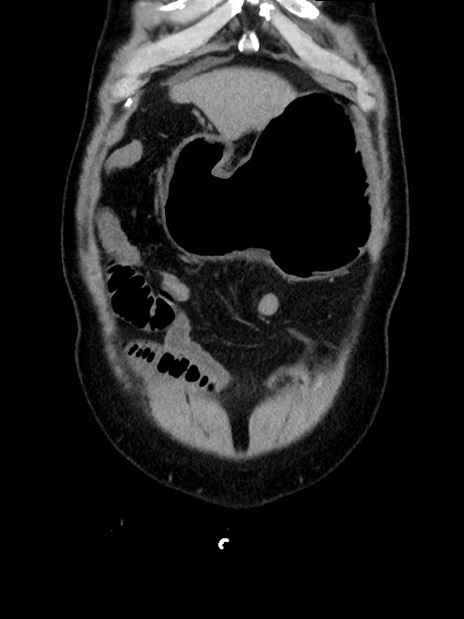

症例35(冠状断像)

【症例】70歳代 男性

【主訴】腹部膨満、嘔吐

【現病歴】昨日より腹部膨満感出現。本日増悪し、仙痛出現。嘔吐あり、受診。

【既往歴】糖尿病、胆摘後

【身体所見】BP 149/80mmHg、HR 74/min、BT 35.9℃、腹部:膨満、軟、圧痛なし。腸雑音減弱あり。上腹部正中切開瘢痕あり。

【データ】WBC 13500、CRP 1.72